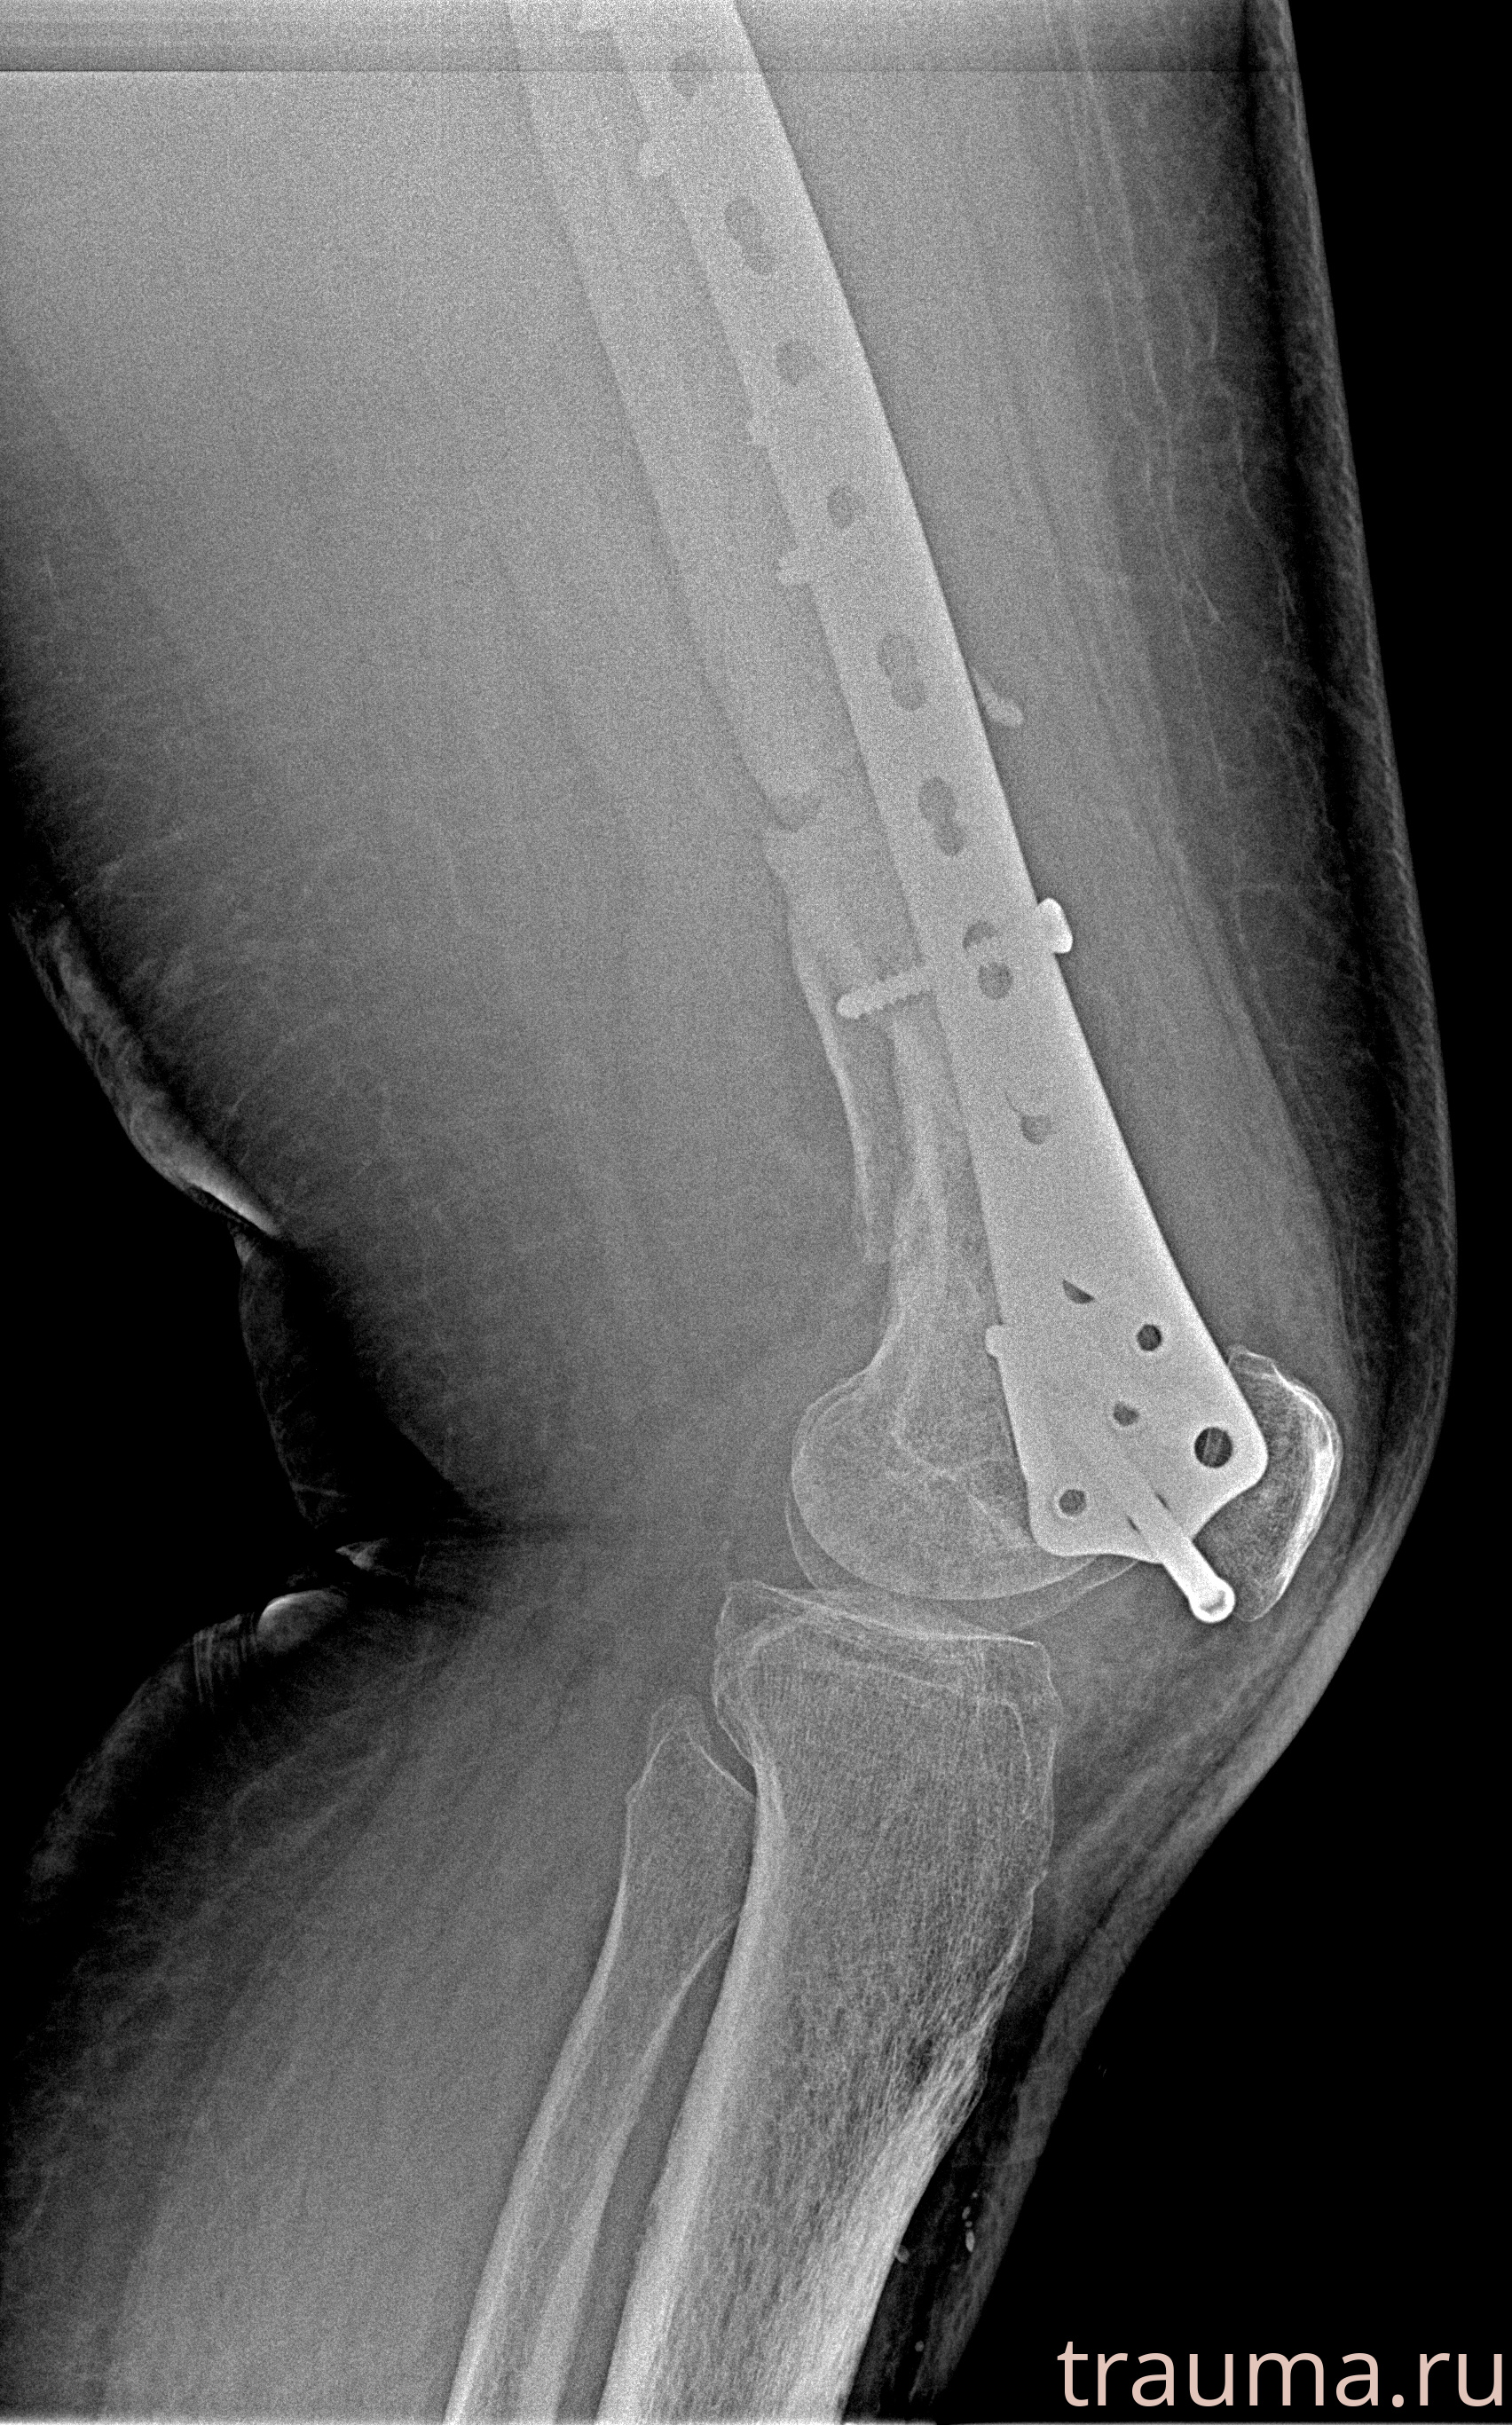

Рентгенограммы

Рентген на дому: по вашему адресу приезжает врач-рентгенолог, травматолог-ортопед с мобильным рентгеновским аппаратом, проводит диагностику травмы или заболевания, делает необходимые рентгенограммы, дает рекомендации по дальнейшему лечению. Получить качественные снимки в домашних условиях возможно благодаря уникальной методике, разработанной МосРентген Центром для института  Склифосовского